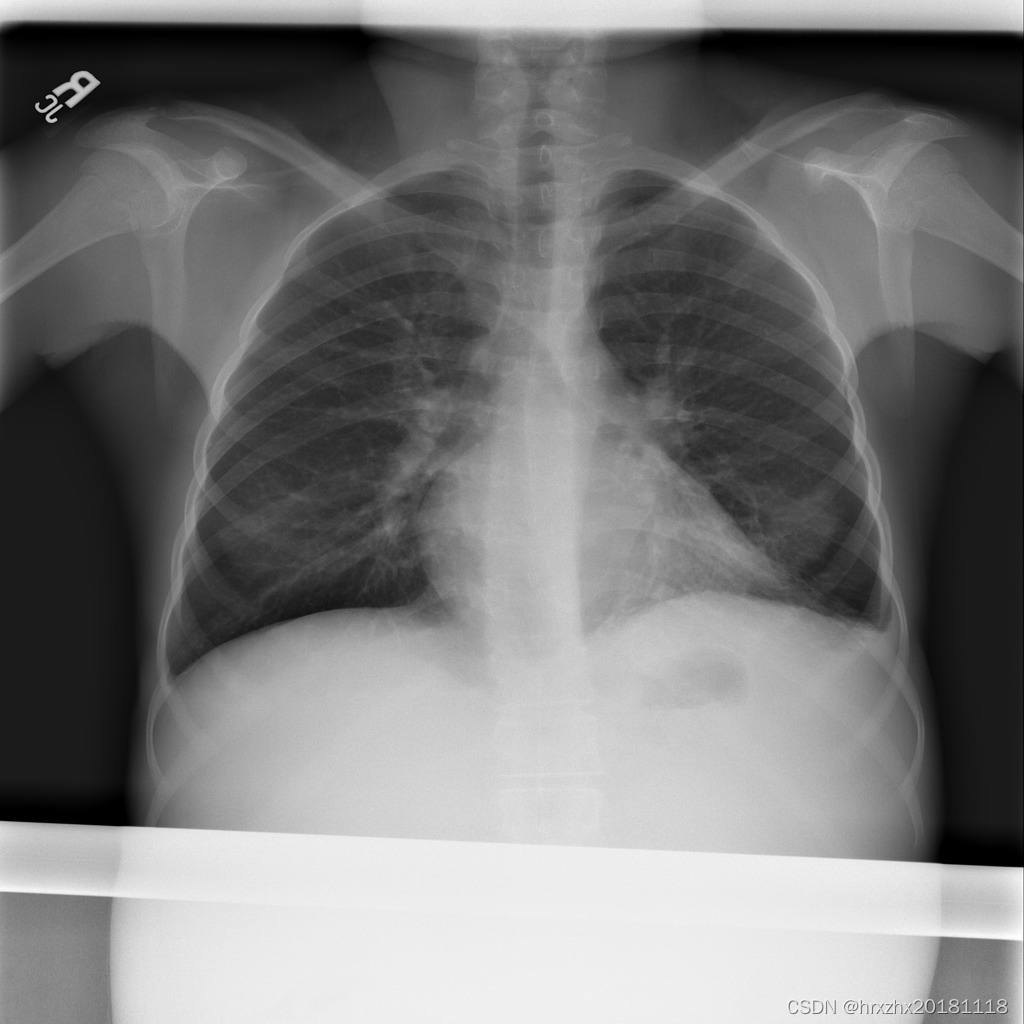

RSNA Pneumonia Detection Challenge(2018年)是由放射学会国家联盟(Radiological Society of North America,简称RSNA)发起的一项挑战,旨在促进和加速肺炎自动检测的研究。该挑战提供了一个公开的数据集,包含了大约30,000名患者的胸部X射线图像,这些图像被标记为是否患有肺炎。数据集中的图像是从多个不同的医疗中心收集而来,涵盖了多种不同的X射线成像系统和设备。

处理好后的带有肺炎标注的VOC目标检测数据集图像总数为6012张,类型标签为病灶区域。